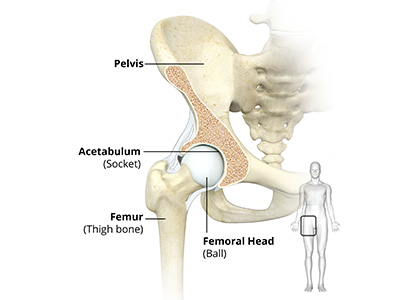

The hip joint is the largest weight-bearing joint in the human body. It is also referred to as a ball and socket joint and is surrounded by muscles, ligaments, and tendons. The thigh bone or femur and the pelvis join to form the hip joint.

The hip joint is the junction where the hip joins the leg to the trunk of the body. It is comprised of two bones: the thigh bone or femur and the pelvis which is made up of three bones called ilium, ischium, and pubis. The ball of the hip joint is made by the femoral head while the socket is formed by the acetabulum. The Acetabulum is a deep, circular socket formed on the outer edge of the pelvis by the union of three bones: ilium, ischium, and pubis. The lower part of the ilium is attached by the pubis while the ischium is considerably behind the pubis. The stability of the hip is provided by the joint capsule or acetabulum and the muscles and ligaments which surround and support the hip joint.

The head of the femur rotates and glides within the acetabulum. A fibrocartilagenous lining called the labrum is attached to the acetabulum and further increases the depth of the socket.

The femur or thigh bone is one of the longest bones in the human body. The upper part of the thigh bone consists of the femoral head, femoral neck, and greater and lesser trochanters. The head of the femur joins the pelvis (acetabulum) to form the hip joint. Next, to the femoral neck, there are two protrusions known as greater and lesser trochanters which serve as sites of muscle attachment.

Articular cartilage is the thin, tough, flexible, and slippery surface lubricated by synovial fluid that covers the weight-bearing bones of the body. It enables smooth movements of the bones and reduces friction.